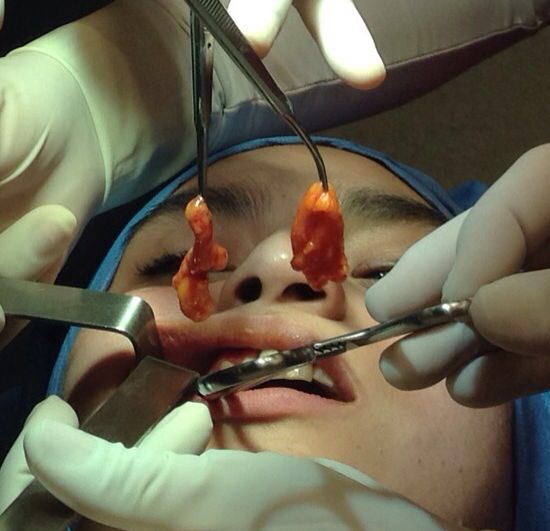

Vean la espectacular transformación 2015, aquí

Da clic en el nombre de nuestros especialista para conocer sus datos y el detalle de lo que le hicieron a Johana

No te pierdas las fotos de todo el proceso de transformación de Johana